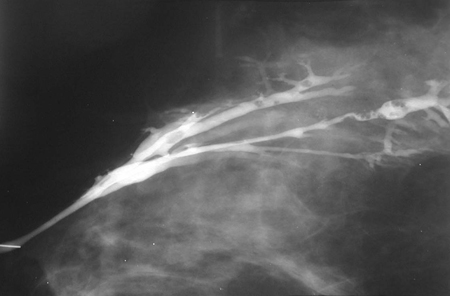

Papiloma mamário

A descarga mamilar sanguinolenta é típica de papiloma mamário. Esse tipo de lesão pode ocasionalmente ser detectado como uma massa dentro da mama. As saliências geralmente ocorrem dentro dos ductos mamários (papilomas intraductais). Essas lesões normalmente são benignas, mas podem estar associadas aos achados histológicos de atipia, carcinoma ductal in situ (CDIS) papilar ou câncer papilar invasivo.[Figure caption and citation for the preceding image starts]: Ductografia demonstrando papilomas intraductais múltiplosCortesia da Dra. Nancy Pile, Universidade de Louisville; usado com permissão [Citation ends].